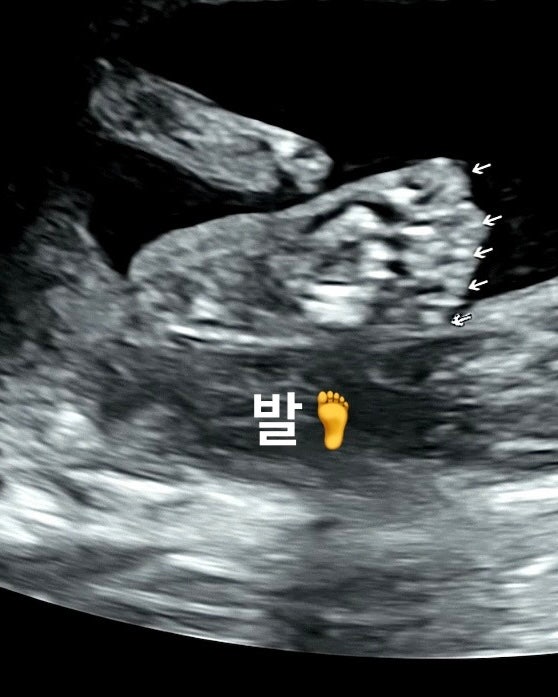

[21주] 2차 정밀 초음파로 손가락, 발가락 10개 확인

아직 태동을 못 느낀 임신 21주차 임신 중기에 진행하는 2차 정밀 초음파 검사를 받았다 2차 정밀은 복부 ...